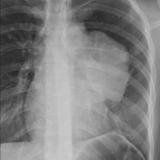

Case 8a Thymoma PA

Date: 03/27/2009

Views: 9448